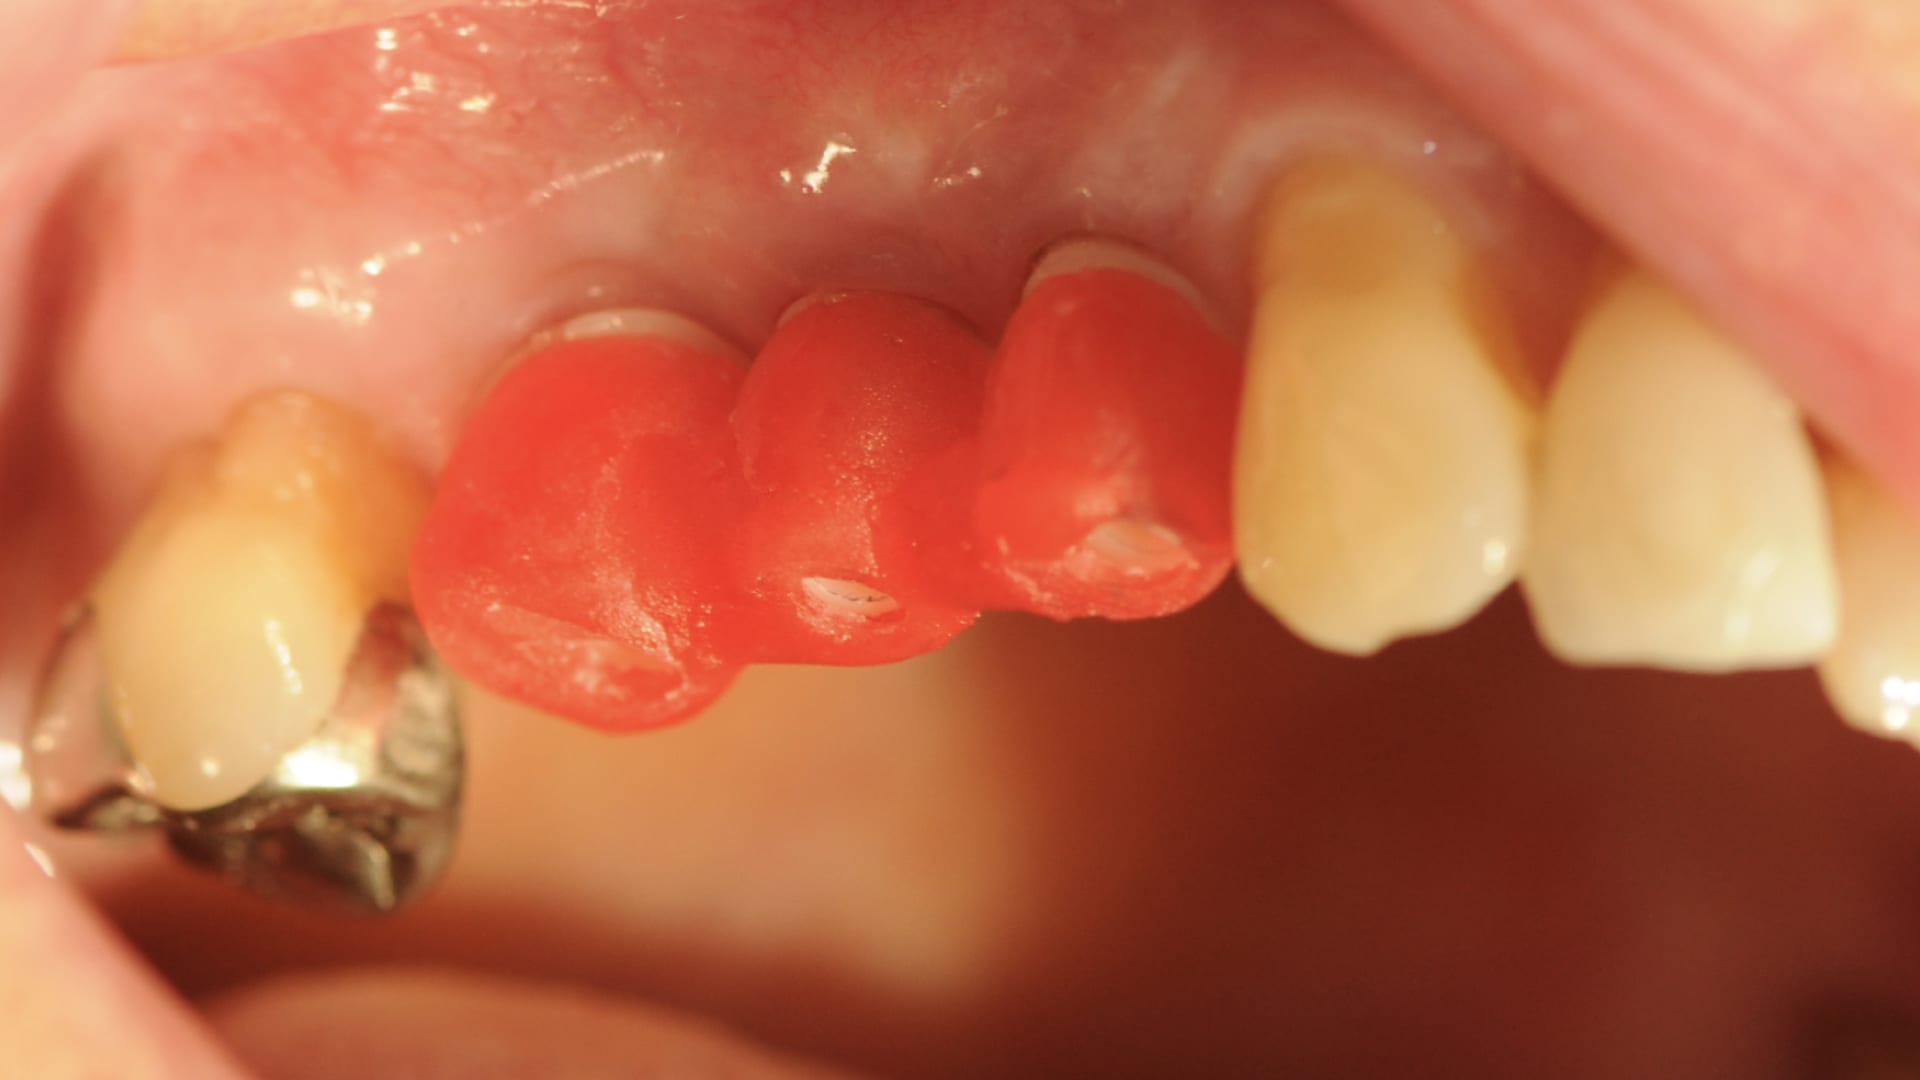

Abb. 2: präoperative Messkugelaufnahme

Die 76-jährige Patientin stellt sich mit einer seit Jahren bestehenden Brückenversorgung im ersten Quadranten in der Praxis vor (Abb. 1). Die Pfeilerzähne 14 und 16 waren seit Jahren wurzelkanalbehandelt. Der mesiale Brückenpfeilerzahn zeigte eine apikale Beherdung mit Parodontalspaltverbreiterung. Insgesamt wies die Brücke einen Lockerungsgrad von 1 bis 2 auf. Die hauszahnärztlich angebotene erneute zahngetragene Brückenversorgung mit Ausdehnung auf den Eckzahn 13 wurde von der Patientin nicht favorisiert. Deshalb wurde der Patientin eine Entfernung der gesamten Brücke mit Sofortimplantation und Sofortversorgung in Nonokklusion angeraten (Abb. 2). Es wurden in Lokalanästhesie drei Straumann Bone Level Tapered Implantate gesetzt. In derselben Sitzung erfolgte die konventionelle Abformung beider Kiefer. Binnen 24 Stunden wurde ein verschraubtes und verblocktes Langzeitprovisorium aus PMMA auf Klebebasen (Straumann) in Nonokklusion erstellt (Abb. 3). Dieses Langzeitprovisorium verblieb 26 Monate in situ. Nach dem Entfernen des Langzeitprovisoriums zeigten sich perfekt ausgeformte Schleimhautemergenzprofile. Es wurden die entsprechenden Scanbodys eingeschraubt. Die Scandaten wurde mit dem 3Shape Trios 3 von Straumann erhoben und dem Labor übersandt (Abb. 4). Die Farbbestimmung erfolgte über den Scanner.